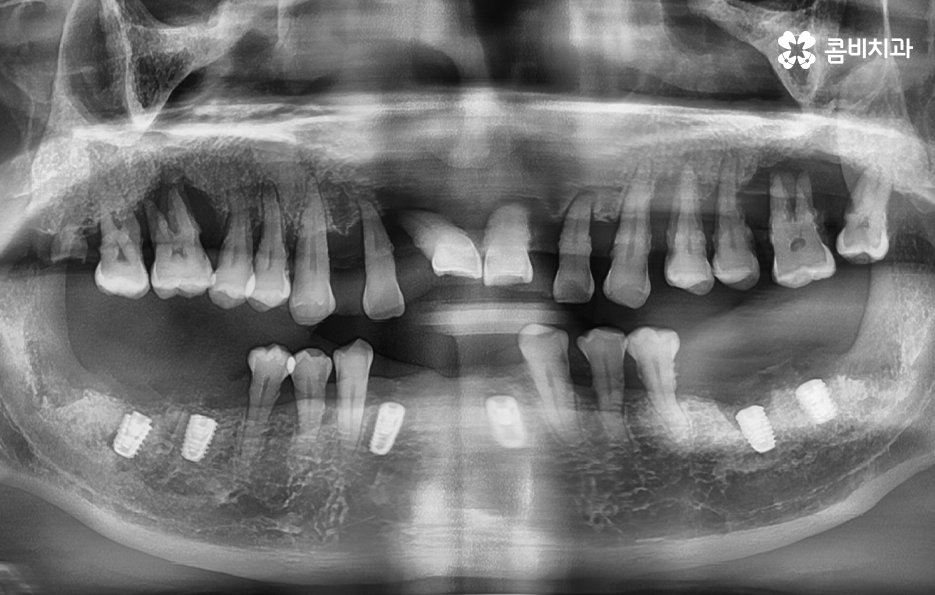

치주염으로 인해 치아를 잃게 되신 분들은 잘 아시겠지만 잇몸이 퇴축되어 있고 잇몸 뼈가 부족하여 임플란트 치료 과정 상에 뼈이식이 필요한 경우가 많고 치아를 한꺼번에 여러 치아를 잃게 되어 임플란트를 여러 개 심어야 하는 경우도 많을 거예요

임플란트의 치료 원리를 살펴보면 임플란트는 잇몸 뼈에 심고 골 유착 과정을 통해서 저작력을 얻기 때문에 치료 전과 치료 후 모두 잇몸 상태가 매우 중요한 치료라는 것을 알 수 있어요

잇몸 뼈가 부족한 경우 뼈이식을 통해 임플란트를 식립하기 좋은 잇몸 상태를 만드는 것이 치료 결과에도 중요하며 임플란트의 식립 위치부터 각도, 깊이 등은 치과의 첨단 장비뿐 아니라 치과의사의 경험과 실력이 중요한 부분이기 때문에 임플란트의 전체 과정을 고려하여 비용도 중요하지만 건강한 치료 결과를 위해 종합적으로 따져보고 치과를 선택하시길 권하고 있어요